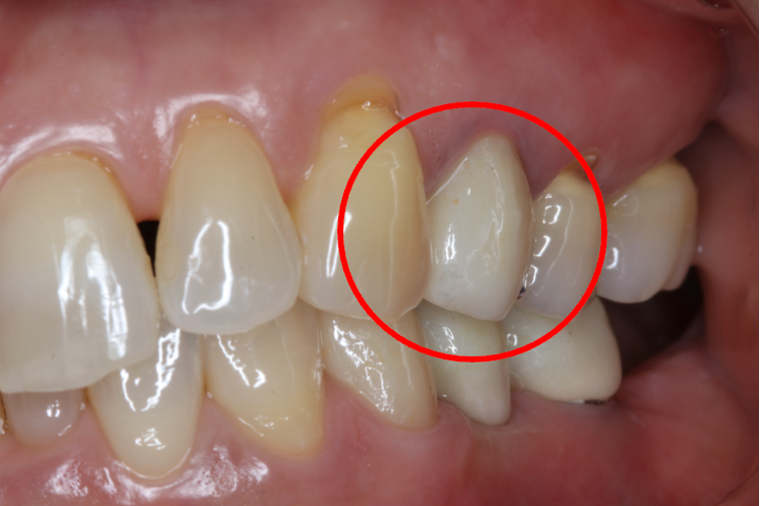

セラミック症例④

年齢50代男性

治療期間1ヶ月

治療内容セラミックインレー、クラウン

治療箇所

左下7番 左上4番、5番、7番 右下6番 右上5番

治療費用600,000円